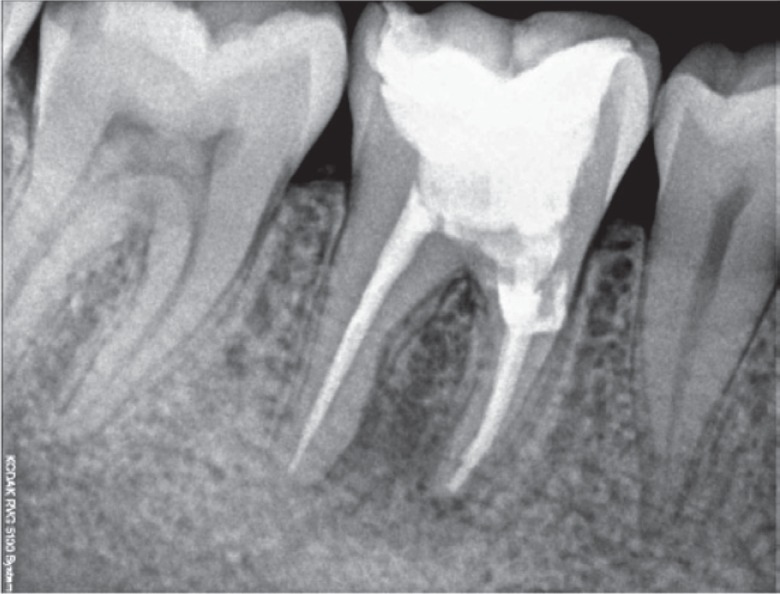

Figure 3). Following the cleaning and shaping of the canals, calcium hydroxide (Avue Cal, Dental Avenue, Param Enterprises, Pune, India) was placed as an intracanal medicament for one and half months. The dressing was changed every two weeks. Once the tooth demonstrated signs of radiographic healing of the periapical lesion and the absence of symptoms, the obturation was completed with cold lateral condensation and resin-based sealer (AH Plus, Dentsply DeTrey, Konstanz, Germany,

Figures 4 and

Figure 4Master cone length radiograph.

Figure 5Post-obturation radiograph.